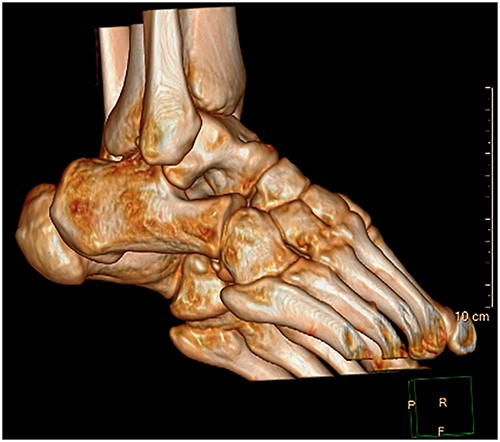

A 28-year-old male patient presented with a history of ankle pain and difficulty with weight-bearing activities on the right side. Radiographic evaluation revealed a large osteochondral defect in the talus. (Figs 1–3).